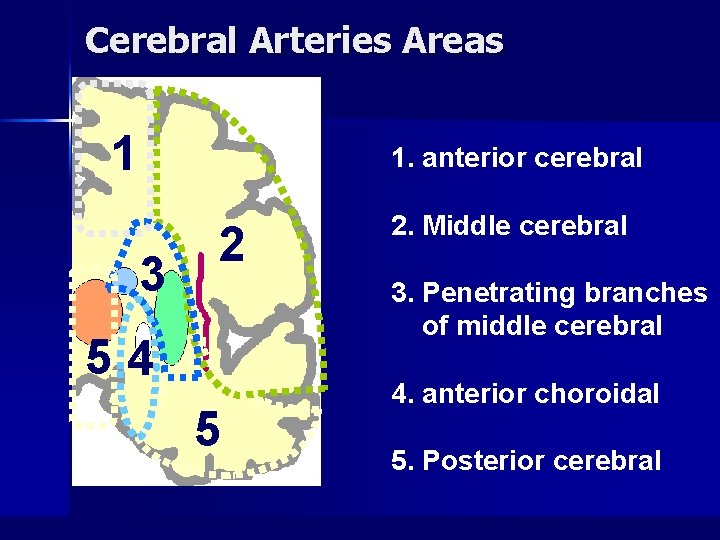

Cerebral Arteries Areas 1 1. anterior cerebral 3 2 2. Middle cerebral 3. Penetrating branches of middle cerebral 54 5 4. anterior choroidal 5. Posterior cerebral